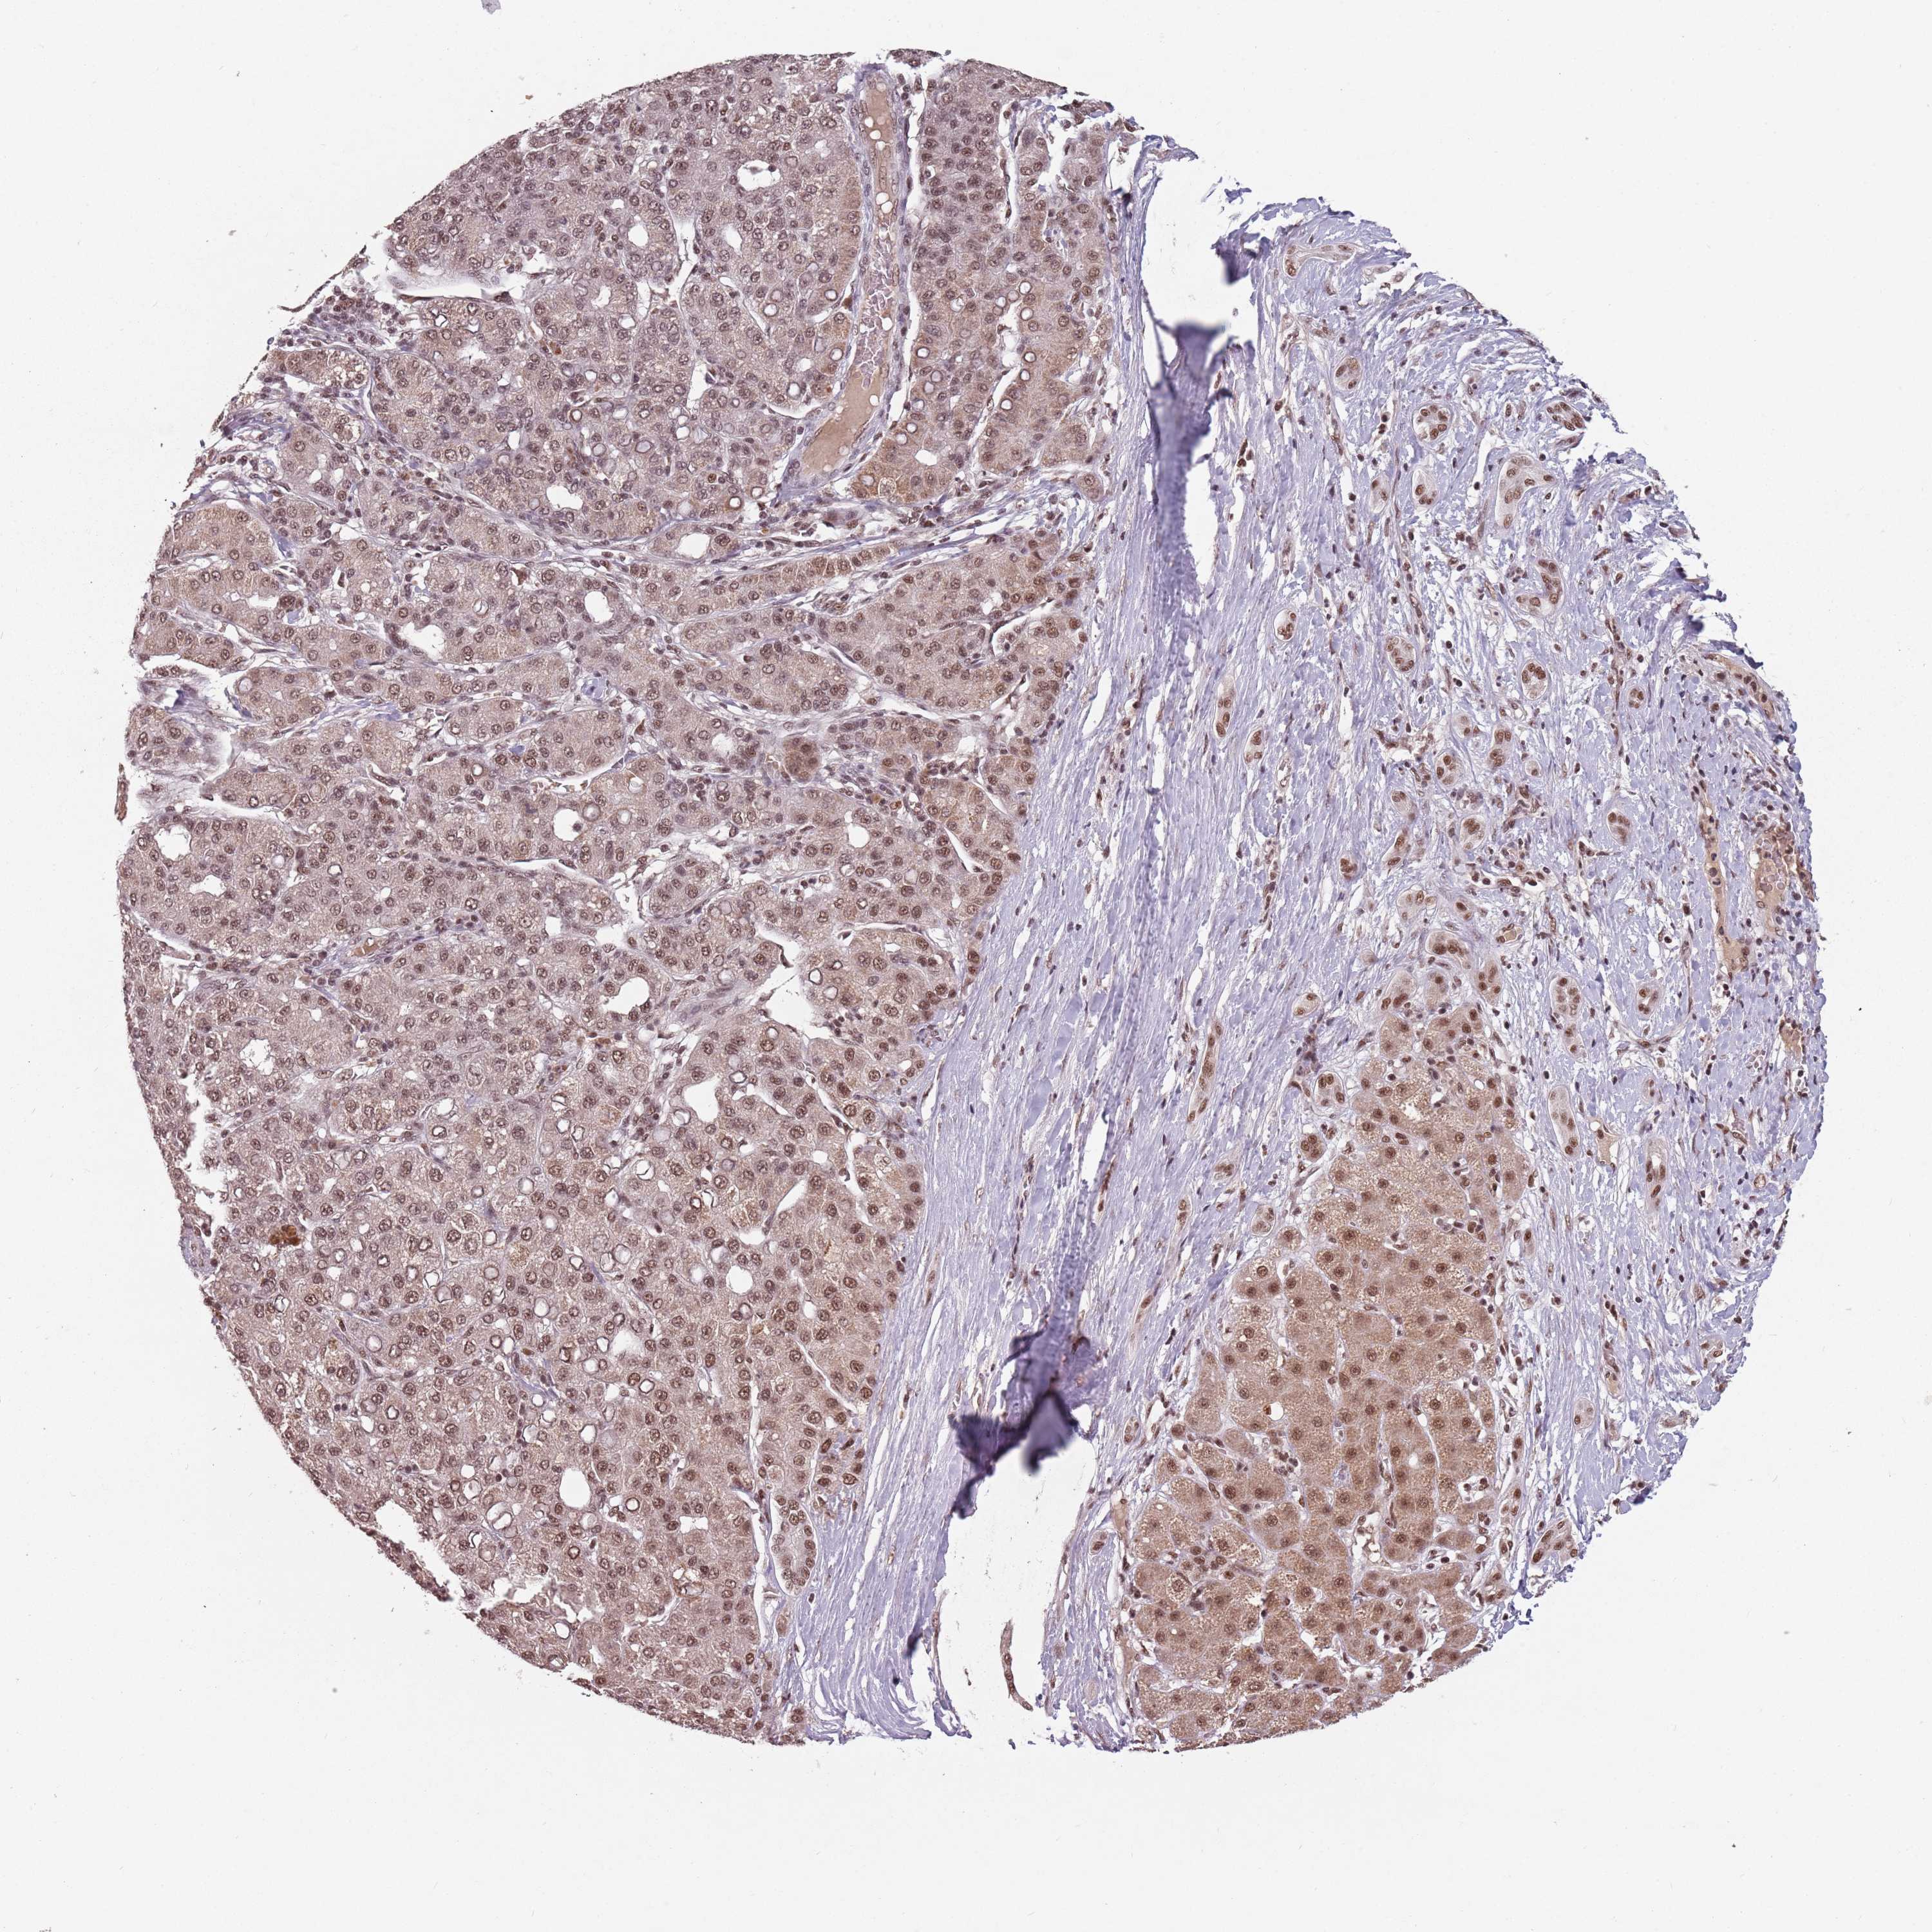

LIVER CANCER - Protein expressioni

A mouse-over function shows sample information and annotation data. Click on an image to view it in a full screen mode. Samples can be filtered based on level of antibody staining by selecting one or several of the following categories: high, medium, low and not detected. The assay and annotation is described here.

Antibody stainingi

Antibody staining in the annotated cell types in the current human tissue is reported as not detected, low, medium, or high, based on conventional immunohistochemistry profiling in selected tissues. This score is based on the combination of the staining intensity and fraction of stained cells.

Each image is clickable and will lead to virtual microscopy that enables deeper exploration of all samples and also displays staining intensity scores, fraction scores and subcellular localization as well as patient and tissue information for each sample.

Antibody HPA049031

Staining

High

Medium

Low

Not detected

Intensity

Strong

Moderate

Weak

Negative

Quantity

>75%

75%-25%

<25%

None

Location

Nuclear

Cytoplasmic/membranous

Cytoplasmic/membranous,nuclear

Cholangiocarcinoma

Carcinoma, Hepatocellular, NOS